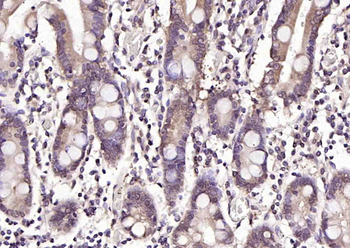

100 μl, 50 μl, 200 μl - HSC70 Mouse Monoclonal Antibody [orb704174]Featured

IF, IHC-Fr, IHC-P, WB

Human, Mouse, Rat

Mouse, Rat

Mouse

Monoclonal

Unconjugated

100 μl, 50 μl, 200 μl - ATF4 Recombinant Rabbit Monoclonal Antibody [orb704304]Featured